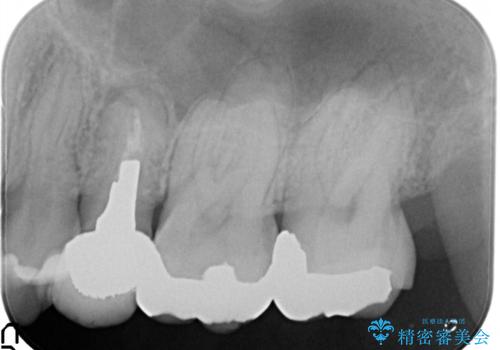

- 左上の後ろから3番目の歯のかぶせ物が適合不良であったので、根管治療を行い、オールセラミックを装着する計画としました。

またその隣の目立つ銀歯も同時に、セラミックに交換することとしました。

根管治療からかぶせ物まで精度の高い治療をおこないました。